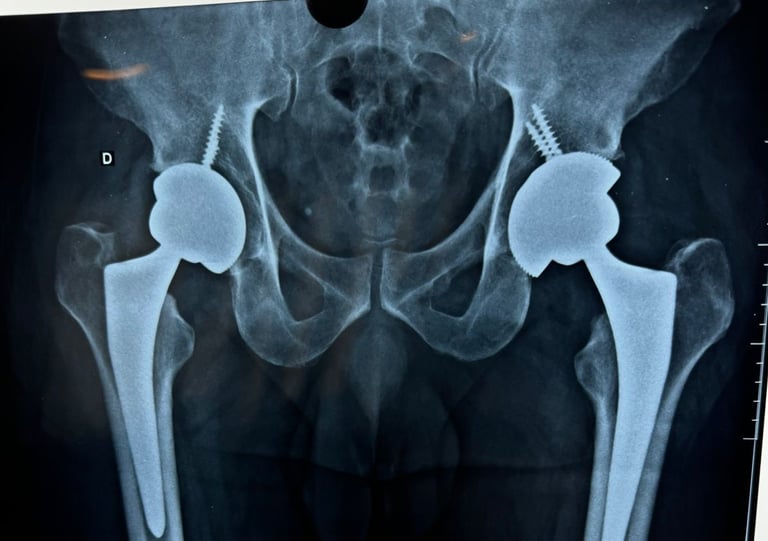

Especialização em Cirurgia de Quadril - Hospital de Base de São José do Rio Preto (SP)/FAMERP